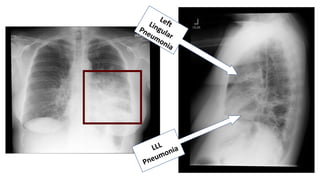

RML pneumonia:

ď‚§ Blurred right heart border

ď‚§ Lateral diaphragm clear

ď‚§ Often seen best on the lateral

RML Infiltrate